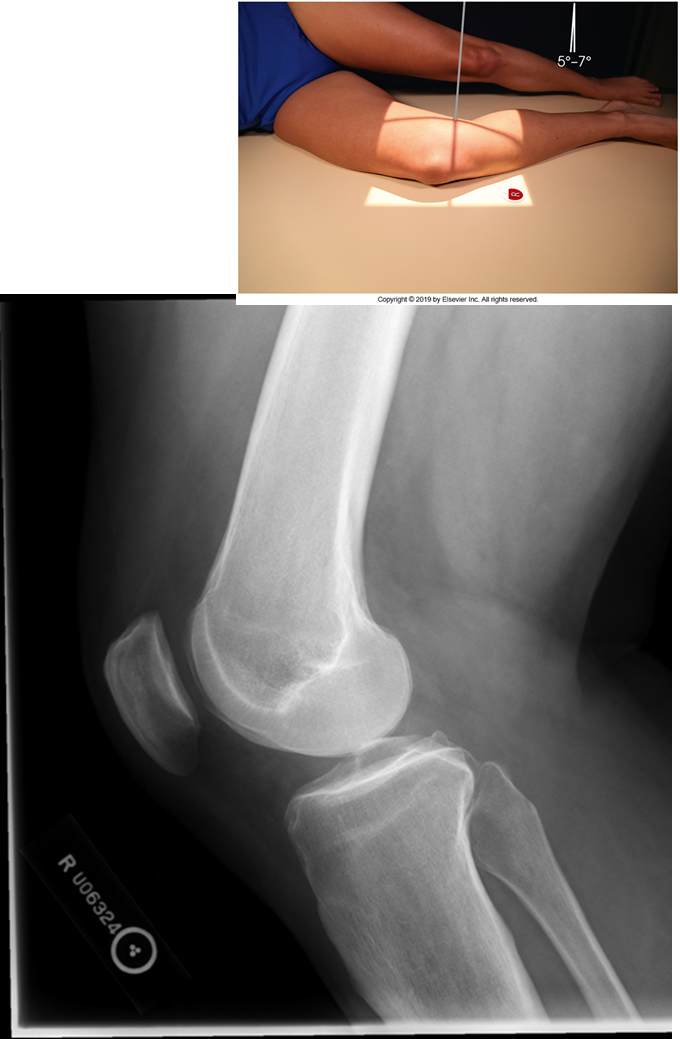

Trauma and Non-Trauma Lateral Knee (Mediolateral)

•Evidence of proper collimation and the presence of a side marker placed clear of the anatomy of interest

•Knee flexed 20 to 30 degrees in true lateral position as demonstrated by femoral condyles superimposed (locate the more magnified medial condyle)

•Anterior surface of medial condyle closer to patella results from over-rotation toward the image receptor (IR).

•Anterior surface of medial condyle farther from patella results from under- rotation away from the image receptor (IR).

•Inferior surface of medial condyle caudal to lateral condyle results from insufficient cephalad central ray (CR) angle.

•Inferior surface of lateral condyle caudal to medial condyle results from too far cephalad CR angle.

•Fibular head and tibia slightly superimposed (over rotation causes less superimposition, and under rotation causes more superimposition)

•Patella in a lateral profile

•Open patellofemoral joint space

•Open joint space between femoral condyles and tibia

•Bony trabecular detail and surrounding soft tissues

over-rotated fibular head is not touching

Patellofemoral joint space is not open (Condyle is in it)

Remove soft tissue of another leg

The medial condyle is closer to the patella it is over rotated

Lateral condyle is lower, too much tube angle

Rotation, fibula is under! Which means it is under-rotated. The condyle is in the patella femoral space, the abductor tubercle (medial condyle) , medial condyle is posterior. Central Ray is too superior. NOT ENOUGH